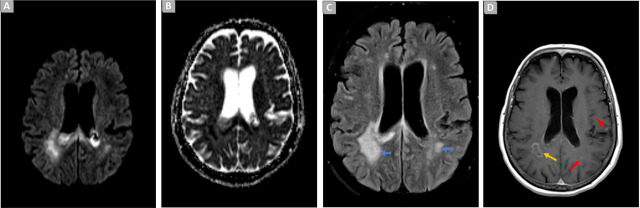

类风湿性关节炎是一种主要影响四肢小关节的炎症性风湿病,经常损害颈椎,导致脊柱不稳,可能需要进行手术治疗。这可能会导致严重的并发症,如脑室炎,通常与高死亡率和耐多药生物有关。如何在中枢神经系统中达到治疗性抗菌浓度是一大挑战。作者介绍了一例 65 岁女性因严重类风湿性关节炎导致颈椎脊髓病变的病例。手术后,患者出现了由广泛耐药的绿脓杆菌引起的脑室炎。早期诊断和及时治疗在促进神经和认知康复方面发挥了至关重要的作用。

Rheumatoid arthritis, an inflammatory rheumatic disease predominantly affecting small limb joints, frequently compromises the cervical spine, resulting in spinal instability and the potential surgical necessity. This may result in severe complications, such as ventriculitis, often associated with a high mortality rate and multidrug-resistant organisms. A major challenge lies in achieving therapeutic antimicrobial concentrations in the central nervous system. The authors present a case of a 65-year-old female, with cervical myelopathy due to severe rheumatoid arthritis. Following surgery, the patient developed ventriculitis caused by an extensively drug-resistant Pseudomonas Aeruginosa. Early diagnosis and prompt treatment played a crucial role in facilitating neurological and cognitive recovery.